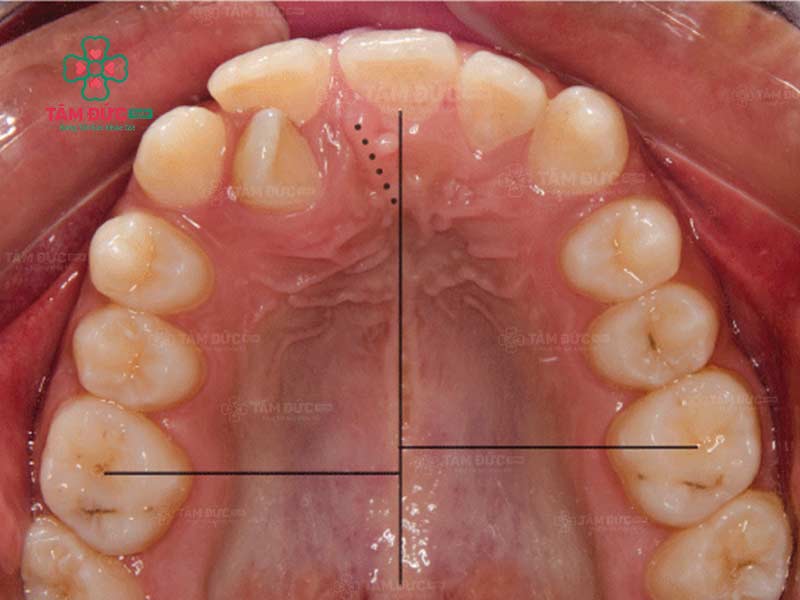

Răng lệch nhân trung là tình trạng kẽ giữa hai răng cửa không nằm thẳng với đường nhân trung. Đường nhân trung là một đường rãnh nhỏ nằm ở giữa mũi và môi trên. Ở người bình thường, kẽ giữa hai răng cửa sẽ nằm ngay trên đường nhân trung. Tuy nhiên, trong một số trường hợp, kẽ giữa hai răng cửa có thể lệch sang trái hoặc phải so với đường nhân trung.

Cách nhận biết Quý khách đang bị lệch nhân trung:

- Nhìn trực tiếp: Quý khách hãy nhìn trực tiếp khuôn mặt của mình trong gương. Nếu Quý khách thấy kẽ giữa hai răng cửa lệch sang trái hoặc phải so với đường nhân trung thì đó là dấu hiệu bị lệch đường giữa.

- Sử dụng thước đo: Quý khách hãy dùng thước đo để đo khoảng cách giữa kẽ hai răng cửa và đường nhân trung. Nếu khoảng cách này không bằng nhau thì đó là dấu hiệu của lệch nhân trung.

Trường hợp bị lệch nhân trung